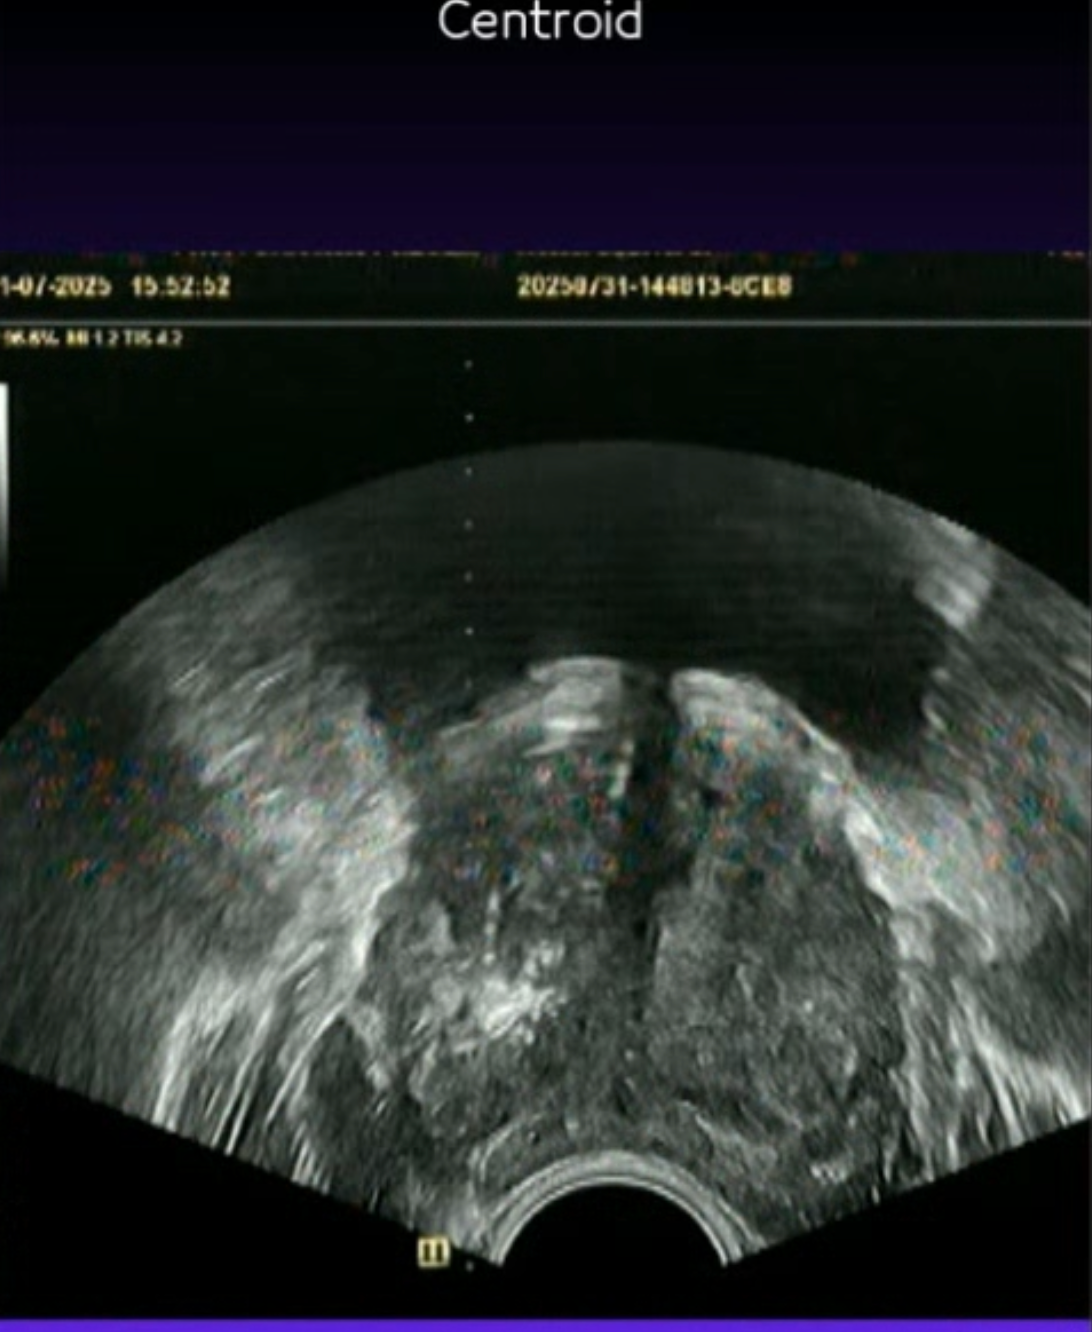

Prostat Füzyon Biyopsi

MR görüntüleri ile ultrason görüntülerinin birleştirilerek hedefe yönelik biyopsi yapılmasını sağlayan akıllı bir teknolojidir.